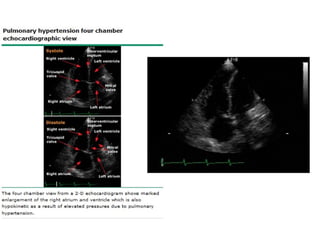

ECOCARDIOGRAMA

• Debe solicitarse siempre ante sospecha de HP.

• Utilidad:

– Estimación de la Presión de la Arteria Pulmonar.

– Tamaño del VD.

– Tamaño de la AD.

– Función Sistólica y Diastólica.

– Función Valvular (principalmente insuficiencia

tricuspidea)

– Shunt Intracardiacos.